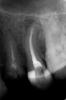

Гиндина Оксана Юрьевна Опубликовано 12 декабря, 2012 Поделиться Опубликовано 12 декабря, 2012 (изменено) Я использую большей частью Крезофен. в каналы стараюсь не вносить ничего. По моему скромному мнению, метапекс и метапасту из каналов не вымыть и не вычистить, ж..проблемы при слепках (ортопеды воют ), каласепт работает только в непосредственном контакте с инфекцией (я против заапекальной терапии) и инактивируется в течение 10 сек на воздухе, а в каналах через несколько часов уже падает ph, становясь "едой" для бактерий. "Не столь важно, что ты положишь в канал. Важно, что ты оттуда достанешь". Намываю до одурения гипохлоридом натрия 3%, активирую соником, жидкий ЭДТА, в конце 2% хлоргексидин и пломбируем на постоянку. в промежутках - на устье Крезофен на PeleTim'e У этого пациента был отек подглазничной области. прошло без внутриканальных паст.. на крезофене. да, пришлось пару посещений просто мыть. Изменено 12 декабря, 2012 пользователем Гиндина Оксана Юрьевна 2 1 Ссылка на комментарий

Prosthodontist Опубликовано 12 декабря, 2012 Поделиться Опубликовано 12 декабря, 2012 Я использую большей частью Крезофен. в каналы стараюсь не вносить ничего. По моему скромному мнению, метапекс и метапасту из каналов не вымыть и не вычистить, ж..проблемы при слепках (ортопеды воют ), каласепт работает только в непосредственном контакте с инфекцией (я против заапекальной терапии) и инактивируется в течение 10 сек на воздухе, а в каналах через несколько часов уже падает ph, становясь "едой" для бактерий. "Не столь важно, что ты положишь в канал. Важно, что ты оттуда достанешь". Намываю до одурения гипохлоридом натрия 3%, активирую соником, жидкий ЭДТА, в конце 2% хлоргексидин и пломбируем на постоянку. в промежутках - на устье Крезофен на PeleTim'e У этого пациента был отек подглазничной области. прошло без внутриканальных паст.. на крезофене. да, пришлось пару посещений просто мыть.верхушка слабовато расширенна крезофен тоже воняет! Ссылка на комментарий

Kivilgar Опубликовано 12 декабря, 2012 Поделиться Опубликовано 12 декабря, 2012 верхушка слабовато расширенна крезофен тоже воняет! А по мне так и нормальная верхушка. Только непонятно что там раздваивается? ход канала или гуттаперча не уплотнена? Ссылка на комментарий

Гиндина Оксана Юрьевна Опубликовано 12 декабря, 2012 Поделиться Опубликовано 12 декабря, 2012 Кактуса слушали?Простите? верхушка слабовато расширенна Да, согласна. Спасибо, доктор. Я показала на снимке важность ирригации, пломбировкой недовольна сама, да и это не вертикалка, а латералка в той клинике, где я работала в тот момент, ничего другого не было.. крезофен тоже воняет! а мне нравится /токсикоманка.../ Ссылка на комментарий

Prosthodontist Опубликовано 12 декабря, 2012 Поделиться Опубликовано 12 декабря, 2012 ну до самой верхушки там еще мм полтора, 25 номер максимум Ссылка на комментарий

Гиндина Оксана Юрьевна Опубликовано 12 декабря, 2012 Поделиться Опубликовано 12 декабря, 2012 А по мне так и нормальная верхушка. Только непонятно что там раздваивается? ход канала или гуттаперча не уплотнена?второе я думаю Ссылка на комментарий

Kivilgar Опубликовано 12 декабря, 2012 Поделиться Опубликовано 12 декабря, 2012 (изменено) ну до самой верхушки там еще мм полтораНе факт, по снимку можно и ошибиться.Да и полтора мм не считается в некоторых случаях недопломбировкой. Изменено 12 декабря, 2012 пользователем Kivilgar Ссылка на комментарий

Kivilgar Опубликовано 12 декабря, 2012 Поделиться Опубликовано 12 декабря, 2012 ну как сказать..Я к тому что по одному этому снимку не взялся бы категорично утверждать о недоработке канала. Мне мало одного виденья снимка без остальной сопутствующей информации. Велика вероятность ошибиться в любом суждении. Ссылка на комментарий